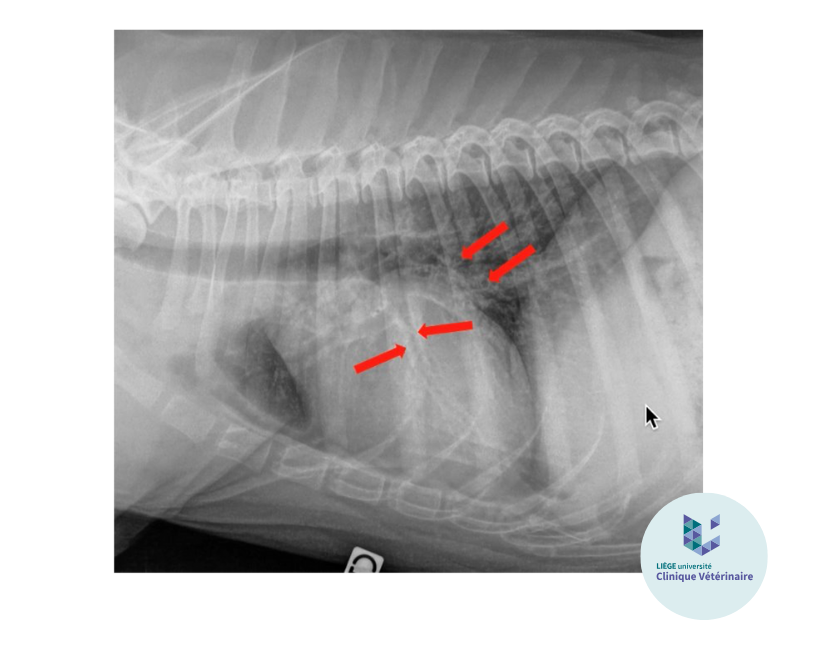

Les bronchogrammes aériques : c’est le signe classique du pattern alvéolaire. La lumière des bronches est bien visible à la radiographie et apparaît comme une arborescence noire s’étendant dans l’opacité du poumon.

Le signe lobaire (= ligne pleurale) : ce signe apparait lorsque le pattern alvéolaire s’étend jusqu'à la périphérie d’un lobe pulmonaire. Il correspond à la démarcation entre le lobe atteint et le lobe adjacent, qui conserve son opacité aérique.